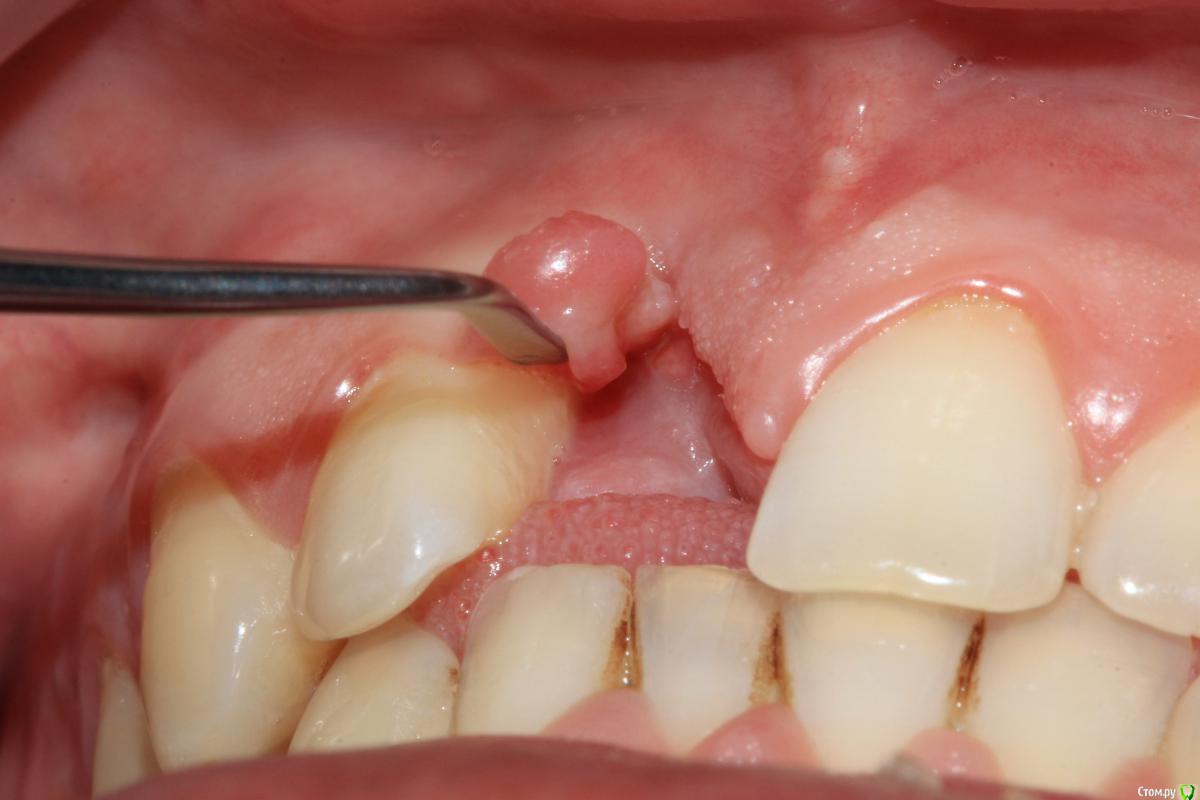

Dc.Petrov Опубликовано 5 мая, 2016 Автор Поделиться Опубликовано 5 мая, 2016 (изменено) медиального пика у 12 нет однозначно, медиальная поверхность корня визуализируется между складками десны Изменено 5 мая, 2016 пользователем Dc.Petrov Ссылка на комментарий

Dc.Petrov Опубликовано 5 мая, 2016 Автор Поделиться Опубликовано 5 мая, 2016 Предполагаю следующий алгоритм:1. Удаление 12 + НКР+ VIP2. Через 5 мес имплантация 11+ ССТ+времяшка3. Постоянное протезирование с консолем на 12. Поправьте,пжста, в чем ошибаюсь. Или как бы Вы поступили в данном случае Ссылка на комментарий

Аслан Опубликовано 11 мая, 2016 Поделиться Опубликовано 11 мая, 2016 Единственный вариант сделать одномоментно с имплантацией нкр - это если вы хорошо можете отработать этот вариант с сеткой, с учетом того, что эта самая сетка "фиксируется" к имплатну заглушкой (посмотрите на форуме темы про необиотек, там показано как) и сразу сможете создать нужный объем десны чтобы эту самую сетку перекрыть и она не экспонировалась. Ссылка на комментарий